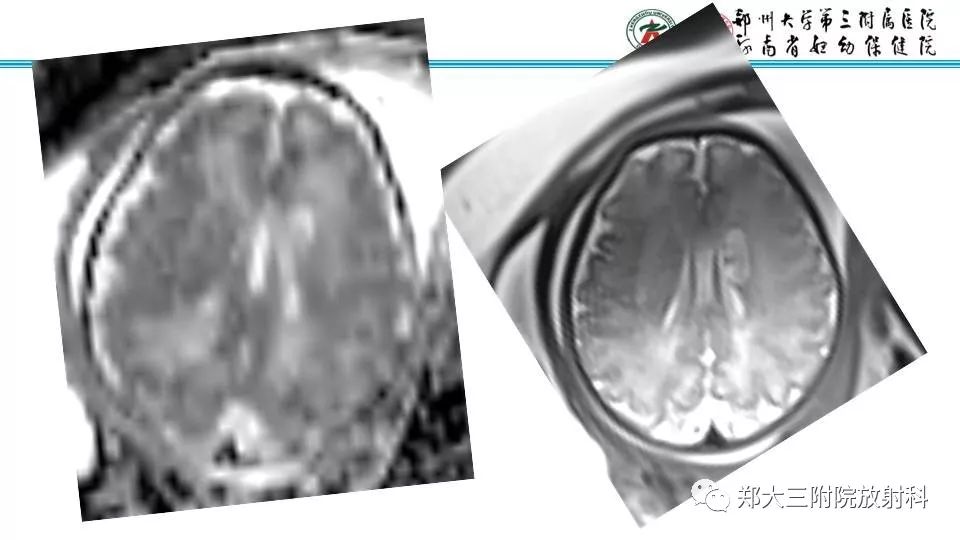

【PPT】室周假性囊肿-3